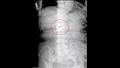

كان الأطباء في حيرة من أمرهم بشأن المكان الذي يمكن أن يذهب إليه طقم الأسنان السفلي وأجروا فحصًا للمريضة المسنة.

وتم إدخال كاميرا في الجهاز الهضمي السفلي للمرأة حيث تم اكتشاف طقم الأسنان في معدتهان ثم تم إزالة المنظار الداخلي وإعادة إدخاله مع غطاء واقٍ لغطاء جسم غريب متصل بالطرف.

وبعد عدة محاولات، تمكن الأطباء من وضع واقي غطاء المحرك فوق طقم الأسنان وإمساكه بملقط أسنان الفئران، وإزالة الجسم الغريب من معدة المرأة.